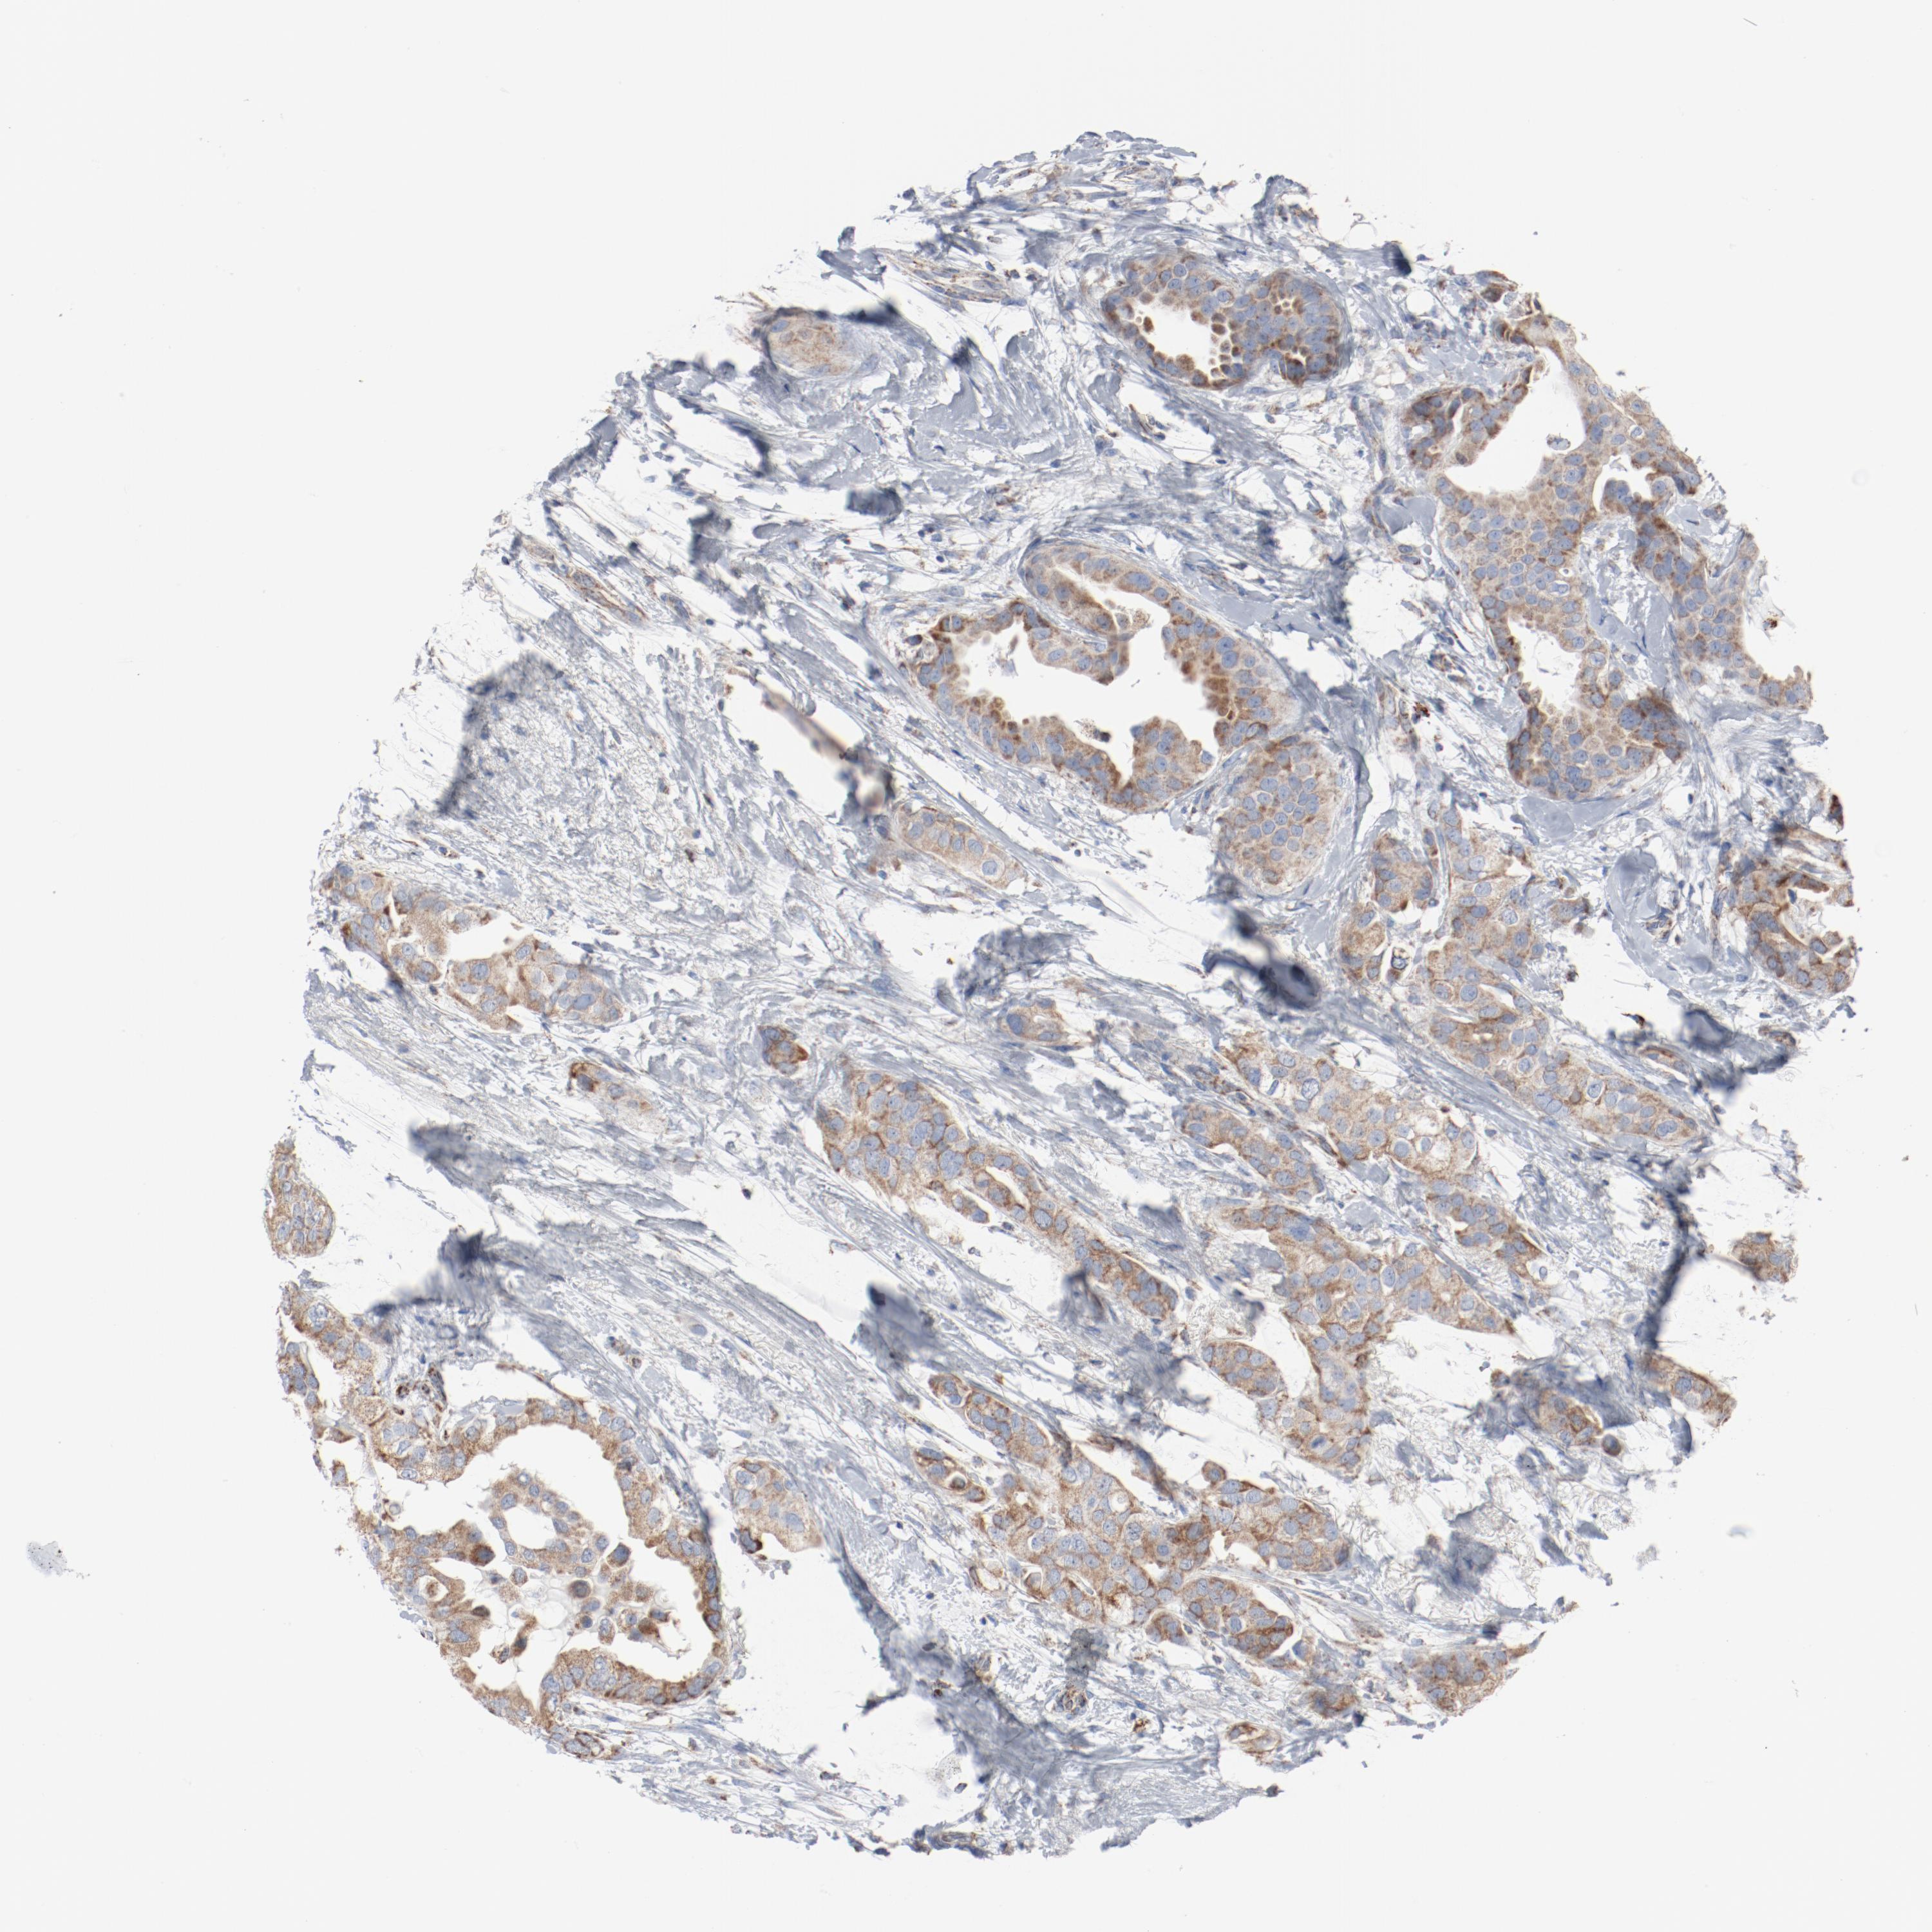

CANCER BREAST CANCER Show tissue menu

BRCA TCGA BRCA VALIDATION PROTEIN EXPRESSION

Breast cancer

Human cancer

NDUFB8 is not prognostic in Breast Invasive Carcinoma (TCGA)